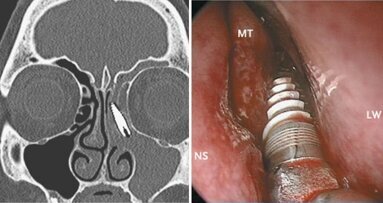

ברשיה, איטליה : חוקרים איטלקים מצאו שתל דנטלי שטייל לתוך חלל הסינוס שלאישה בת 57, ...